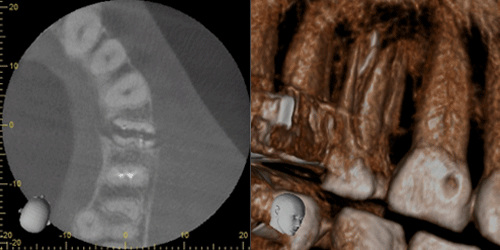

口腔外科治療とCT

親知らずや、埋伏歯の診断に利用することで、立体的に歯の位置や、顎骨の状態、周囲の神経や血管の管との関係を明確に診断できます。 それにより治療の安全性が高まり、患者様にとっても有益となります。のう胞や腫瘍に関しては、その位置や大きさなどを立体的に確認でき、その後の治療計画、処置に役立ちます。顎関節症、歯性上顎洞炎などの疾患に関しても、今までのレントゲンでは得られなかった情報を得れることで診査診断、治療に多く貢献できます。